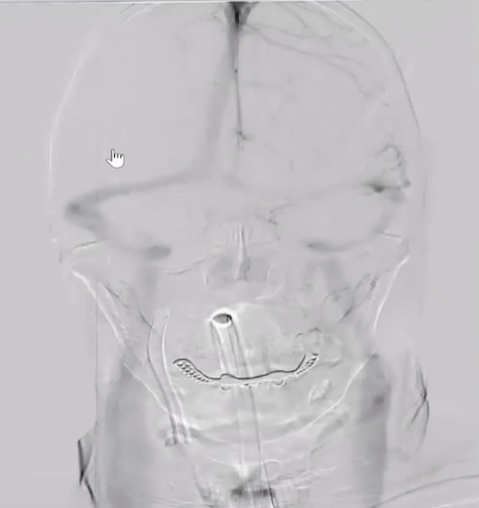

术前检查

病历夹什么径技·第152期|串联营病历夹:川陕大营_https://www.jmylbn.com_新闻资讯_第59张

病历夹什么径技·第152期|串联营病历夹:川陕大营_https://www.jmylbn.com_新闻资讯_第60张

病历夹什么径技·第152期|串联营病历夹:川陕大营_https://www.jmylbn.com_新闻资讯_第61张

<<滑动查看下一张图片>>

初步诊断:1.脑梗死(右)急性期2.右侧颈内动脉起始部次全闭塞3.右侧大脑中动脉M1段血栓形成

手术方案

• 术前评估:患者发病3小时,头颅CT排除颅内出血,急性起病,突然出血言语不利,左侧肢体麻木无力,鼻唇沟左浅,口角左低,伸舌偏左,左侧Babinski症(++),右侧阴性。患者急性脑梗死诊断明确,发病后症状持续加重,考虑大血管事件。患者无急诊DSA禁忌,建议行DSA检查,必要时介入治疗。经过与家属充分沟通,家属理解手术风险,同意手术治疗。故选择右侧股动脉穿刺置管,先行脑血管造影术,之后再明确下一步治疗方案。

• 药物准备:1、术前顿服300mg阿司匹林+300mg硫酸氢氯吡格雷2、术中充分肝素化

• 手术方案:急诊右侧颈动脉起始部球囊扩张+支架置入术+取栓术

• 术中涉及介入器械材料:8F动脉鞘、5F单弯导管、6F抽吸导管、8F导引导管、0.017in微导管、0.035in泥鳅导丝、0.018in交换导丝、0.014in微导丝、球囊Boston Scientific Sterling MR、支架Boston Scientific Carotid WALLSTENT、保护伞Boston Scientific FilterWireEZ